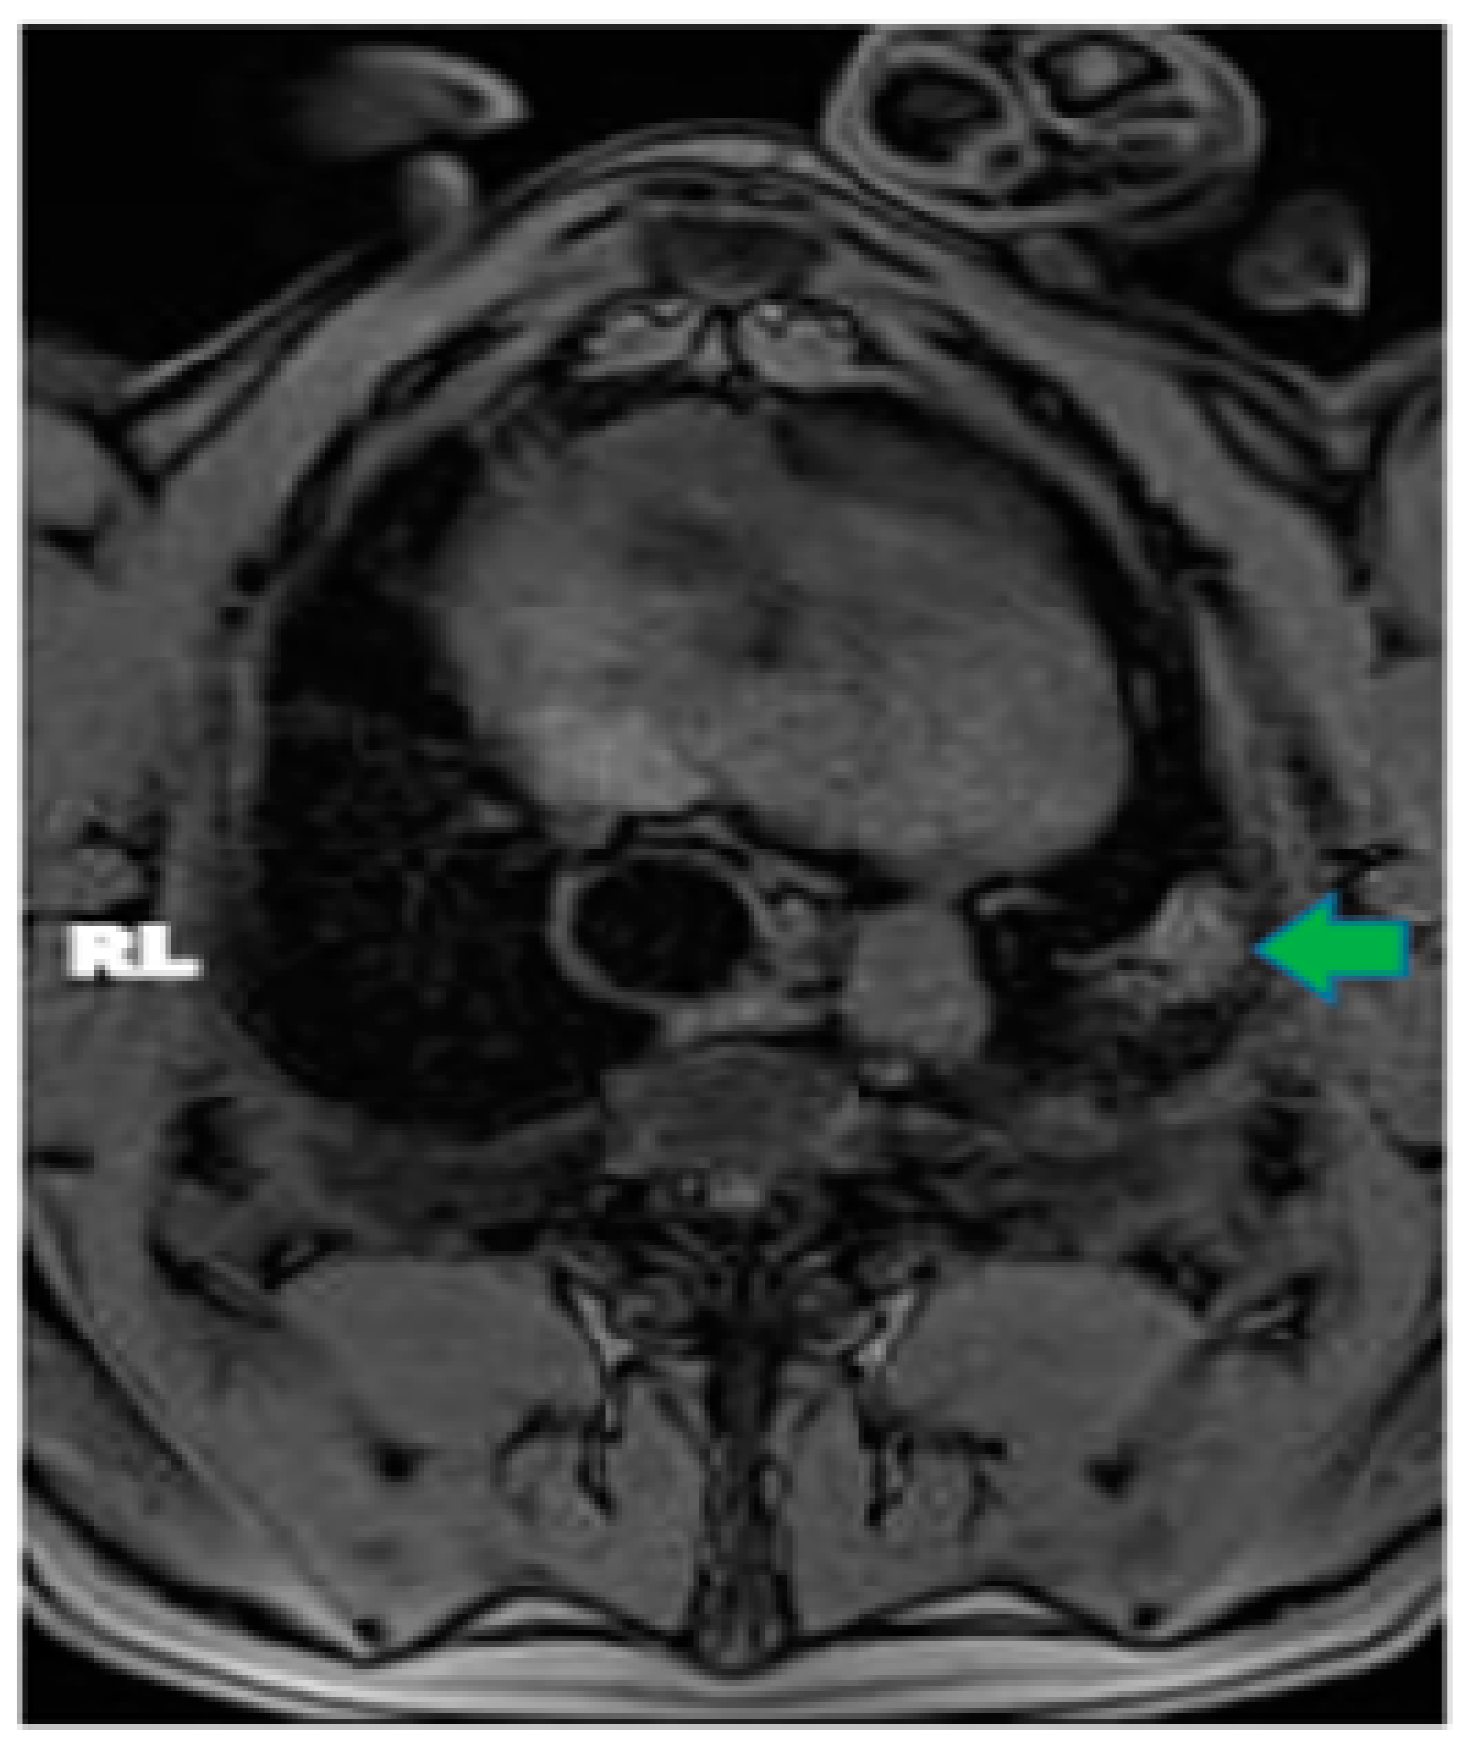

In pig #2, the aim was to study the health effects following MRgFUS with multiple (six) doses of a higher power delivered at six different locations but using only two intercostal/skin areas as entry points. Following the six treatments with MRgFUS at 350 Watts for 20 s each, mild burn marks were visible on the skin at the FUS beam entry points. The pig recovered successfully from the anesthesia. Mild wheezing was noticeable in the week-long post-treatment follow-up. After one week, the pig was scanned using MRI and had hyper-intense regions in the left lung that corresponded with the treatment locations (an example is shown Figure 2). The pig was then euthanized and examined utilizing gross histology. At the locations of the MRgFUS treatment, there were dense fibrotic tissues with white discoloration, indicating successful lung parenchyma ablation (Figure 3A). There was no damage observed on the pericardium or heart.

Furthermore, all of the subsequent pigs showed successful ablations in the one-week post-treatment MRI and in their gross histology, with the tissue corresponding to the targeted areas having a hard and fibrotic consistency upon necropsy (Figure 3B). The lung tissue biopsies of the healthy and targeted tissue were examined using histology and confirmed that the FUS-targeted tissues presented a denser fibrotic consistency instead of normal alveolar structures and red blood cells (Figure 4). Pig #9 was unique in that there was a wedge-shaped lesion in the upper right lung. This lesion may have been due to reflection of the MRgFUS beam off the opposing ribcage, as the largest section of the wedge was closest to the ribcage. All of the pigs remained healthy during the post-treatment follow-up week, with no noticeable health complications.

Figure 2. Axial MRI view of pig #8, one-week post MRgFUS ablation treatment. Green arrow points to ablated area in left lung.